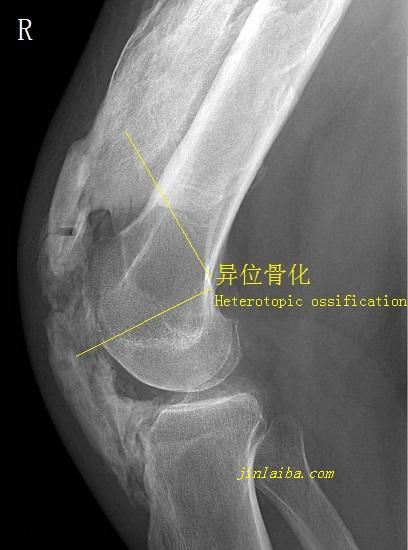

关节僵硬与肌肉失用、协调性丧失、感觉缺失有关。关节长期失用并静止不动的情况下,骨骼、软组织会逐渐退化,纤维化组织出现增生,如果再因为外力引发损伤,还可能会出现异位骨化和软组织粘连,造成难以逆转的关节僵硬。防止关节僵硬的方法有:防止外伤;适当运动(包括被动运动);关节活动度训练。